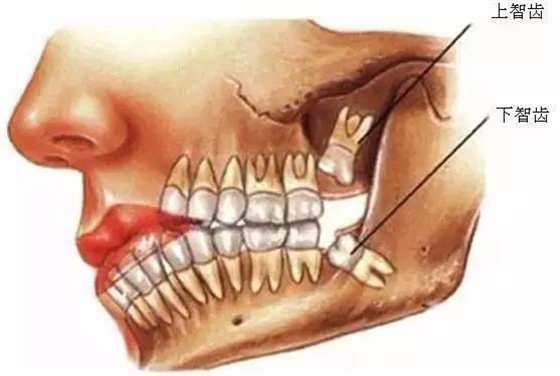

口腔醫(yī)院牙醫(yī)表示,智齒這個(gè)磨人的小妖精,簡(jiǎn)單的說(shuō)就是人類演化過(guò)程的棄兒。觀察古人類和其他靈長(zhǎng)類的頜骨,會(huì)很容易發(fā)現(xiàn),他們的頜骨與現(xiàn)代人相比更大,頰舌面寬度更寬,近遠(yuǎn)中向長(zhǎng)度更長(zhǎng)。頜骨空間充足,智齒的生長(zhǎng)方向和咬合關(guān)系一般都比較正常,很少出現(xiàn)現(xiàn)代人智齒阻生的情況,說(shuō)明頜骨提供的空間跟智齒的萌出狀態(tài)有直接的關(guān)系。

所以,簡(jiǎn)單的說(shuō)智齒實(shí)際上是人類演化過(guò)程中被放棄的生物學(xué)性狀,由于個(gè)體遺傳基因的不同,在這個(gè)性狀的表達(dá)上存在差異,是否萌出智齒以及萌出數(shù)量都因人而異,有人是4顆全部萌出,有人只萌出1顆,也有人1顆智齒也不長(zhǎng)的。

6、阻生齒

一般這是最討厭的一種,牙醫(yī)會(huì)覺(jué)得很難搞定,但患者卻不一定有感受,因而忽略了。這一種類型的牙齒,一般埋在齒槽骨的里邊,假如會(huì)痛,或是確診會(huì)有病灶發(fā)作的時(shí)分,就需求拔除了。